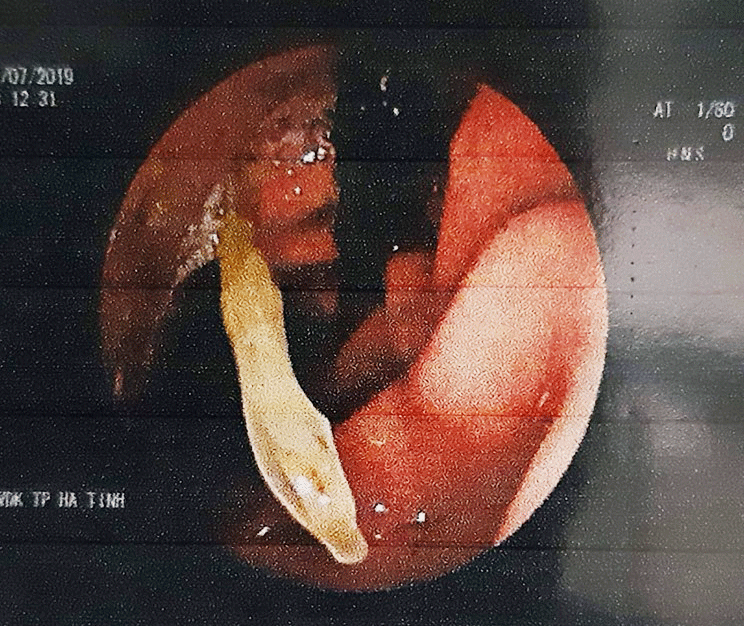

| Hình ảnh nội soi dạ dày bệnh nhân cho thấy que tăm đang nằm ngang dạ dày. (Ảnh: BVCC). |

Sau khi siêu âm, các bác sĩ xác định bệnh nhân này bị nhiễm trùng dạ dày. Trong quá trình nội soi, bác sĩ CKI Hồ Văn Khiêm - Khoa Nội (Bệnh viện đa khoa TP Hà Tĩnh) phát hiện trong dạ dày bệnh nhân có dị vật nằm ngang. Khi bơm rửa sạch thì đó là một que tăm, các bác sĩ sau đó đã soi gắp que tăm ra khỏi dạ dày cho người bệnh.